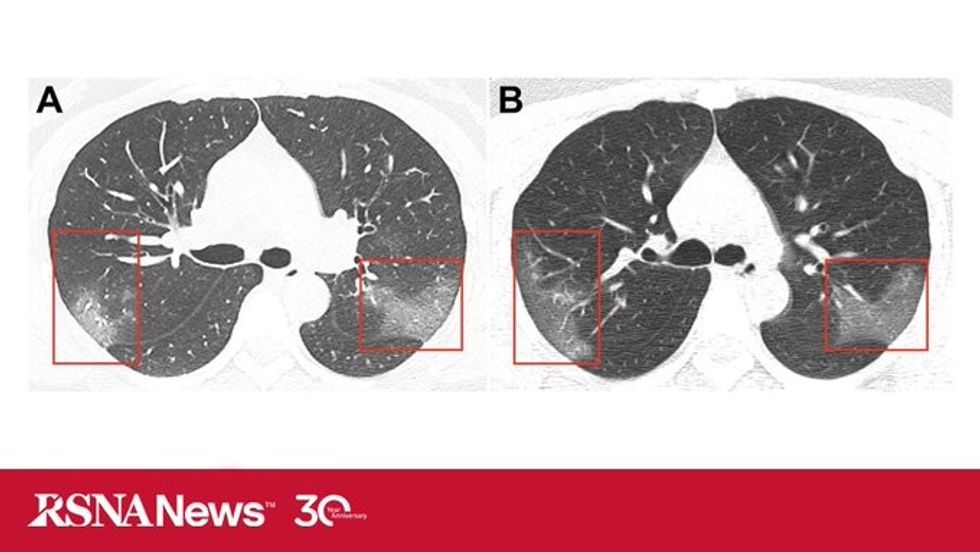

Në imazhe mjekët kanë hasur në hije të bardha të njohura si xhamat e qumështit, që paralajmërojnë se mushkëritë pjesërisht janë të mbushura me lëngje.

Imazhet janë publikuar në revistën shkencorë Radiology, kurse tekstin e kanë përpiluar ekipi i mjekëve të spitalit në Landzou. Ata pretendojnë se pacientët e infektuar me coronavirus, fillimisht vërejtën se kanë infeksione që mund të dëmtojnë mushkëritë dhe të shkaktojnë ndezjen e tyre që kërcënon jetën e njeriut.

Sipas tyre mushkëritë mbushen me lëngje, dhe për këtë arsye mjekët menjëherë u japin terapinë që u ndihmon në hapjen e kanaleve të frymëmarrjes.

Mjekët paralajmërojnë së në fillim shumë lehtë mund të ngatërrohet coronavirusi me ndezjen e mushkërive. Megjithatë imazhet e rëntgenografisë kanë treguar se pas tre ditëve gjendja e pacientit përkeqësohet siç ka ndodhur në raste me SARS dhe MERS, viruse këto gjithashtu që kishin shpërthyer në Kinë. /Telegrafi/